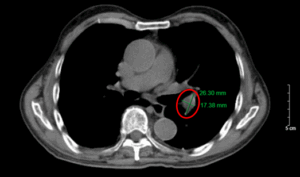

Điều trị đích bệnh nhân ung thư phổi không tế bào nhỏ có tổn thương di căn gan tại Bệnh viện Bạch Mai

Điều trị đích bệnh nhân ung thư phổi không tế bào nhỏ có tổn thương di căn gan tại Bệnh viện Bạch Mai GS. TS. Mai Trọng Khoa, PGS. TS. Phạm Cẩm Phương, PGS. Phạm Văn Thái, TS. Nguyễn Thanh Hùng, BSCKII. Thiều Thị Hằng, BSNT. Nguyễn Văn Sơn Trung...